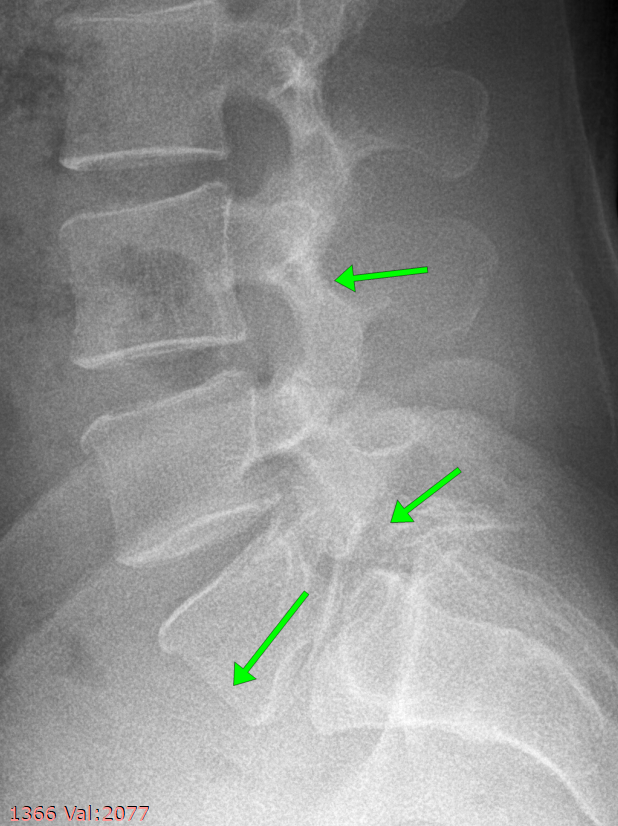

Делаем рентген, смотрим улику № 2.

Имеется несращение кости (дужки). Это аномалия развития, которая называется Spina bifida.

Смотрим сбоку.

Верхняя стрелка - нормальная дужка.

Нижняя - несращение дужки и соответственно смещение позвонка.

При сгибании и разгибании оцениваем степень нестабильности.

Степень нестабильности небольшая, менее 25% длины тела позвонка. Это означает что пока что можно полечиться консервативно.